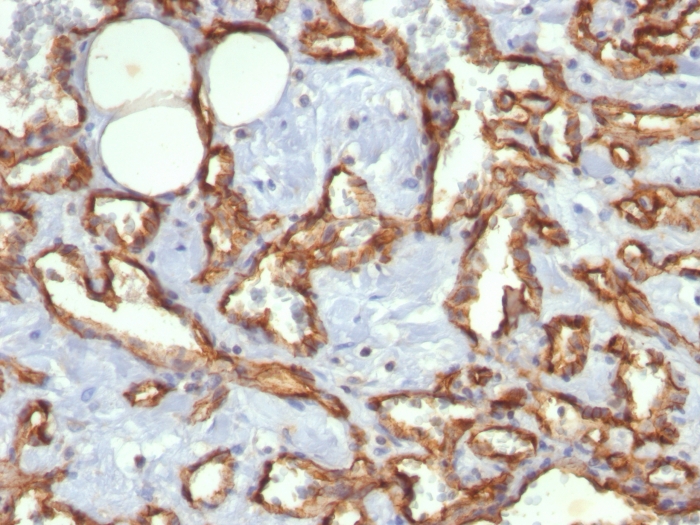

Formalin-fixed, paraffin-embedded human Angiosarcoma stained with CD31 Mouse Monoclonal Antibody (C31.3).

CD31 (PECAM-1) is a transmembrane glycoprotein member of the immunoglobulin supergene family of adhesion molecules. CD31 is expressed by stem cells of the hematopoietic system and is primarily used to identify and concentrate these cells for experimental studies as well as for bone marrow transplantation. Anti-CD31 has shown to be highly specific and sensitive for vascular endothelial cells. Staining of nonvascular tumors (excluding hematopoietic neoplasms) is rare. CD31 MAb reacts with normal, benign, and malignant endothelial cells which make up blood vessel lining. The level of CD31 expression can help to determine the degree of tumor angiogenesis, and a high level of CD31 expression may imply a rapidly growing tumor and potentially a predictor of tumor recurrence.